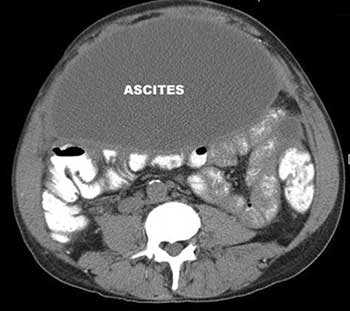

Асцит — патологическое состояние, при котором в брюшной полости скапливается жидкость. Причины его бывают различными. Чаще всего к асциту приводит цирроз печени. Так же он возникает как осложнение онкологических заболеваний, при этом ухудшается состояние больного, снижается эффективность лечения.

Асцит - это вторичное состояние, характеризующееся накоплением экссудата или транссудата в свободной брюшной полости. Клинически проявляется увеличением объема живота, тяжестью, чувством распирания и болями в брюшной полости, одышкой. Диагностика асцита включает проведение УЗИ, КТ, УЗДГ, диагностической лапароскопии с исследованием асцитической жидкости. Для патогенетического лечения необходимо установить причину, вызвавшую скопление жидкости; к симптоматическим мероприятиям при асците относятся назначение мочегонных средств, пункционное удаление жидкости из брюшной полости.

Асцит (другое название - «водянка живота») характеризуется избыточным скоплением свободной жидкости в брюшной полости. Основными причинами (механизмами) развития асцита могут стать повышенное давление венозной системы, пониженное содержание альбуминов в плазме крови, гиперпродукция жидкости, а также нарушенный отток лимфы (лимфостаз).

Асцит является следствием печеночных нарушений в 70 % случаев; онкопроцессов - в 23 %; заболеваний сердечно-сосудистой системы - в 7 % случаев. Клинически у больного наблюдается увеличение размеров живота и значительное увеличение массы тела.